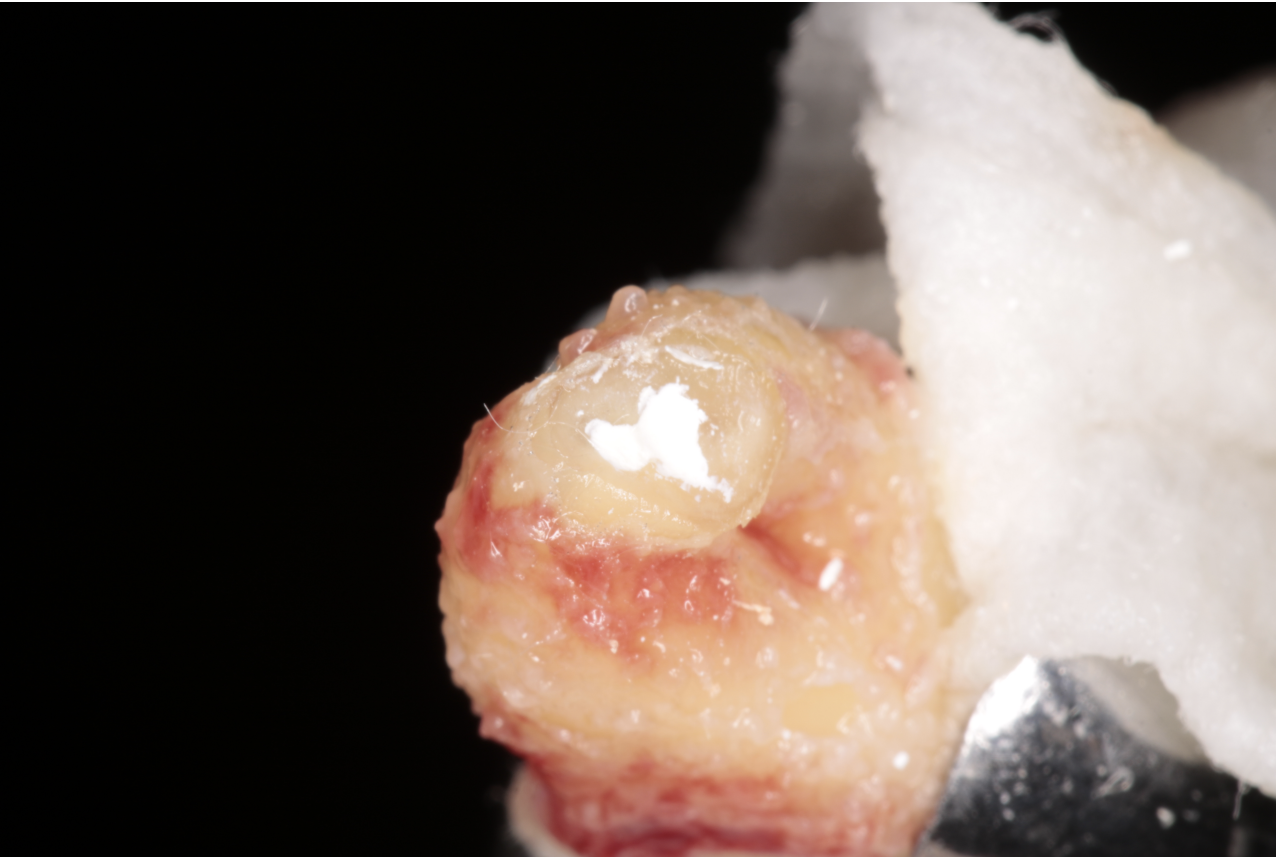

Autotrasplante

Consiste en la movilización de un diente al alvéolo de un diente que ha sido previamente extraído, estando indicado en pacientes en jóvenes y en crecimiento.